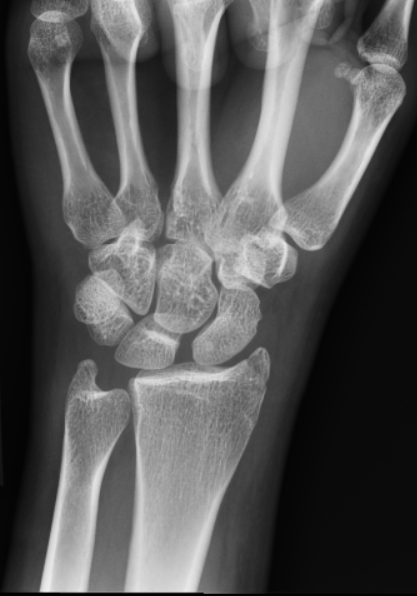

What’s the Diagnosis? Gepost op 18 januari 201818 januari 2018 door netwerkvsseh What’s the Diagnosis? @emdaily.cooperhealth.org Dit delen: Delen op X (Opent in een nieuw venster) X Share op Facebook (Opent in een nieuw venster) Facebook Delen op LinkedIn (Opent in een nieuw venster) LinkedIn E-mail een link naar een vriend (Opent in een nieuw venster) E-mail Afdrukken (Opent in een nieuw venster) Print Vind-ik-leuk Aan het laden... Gerelateerd